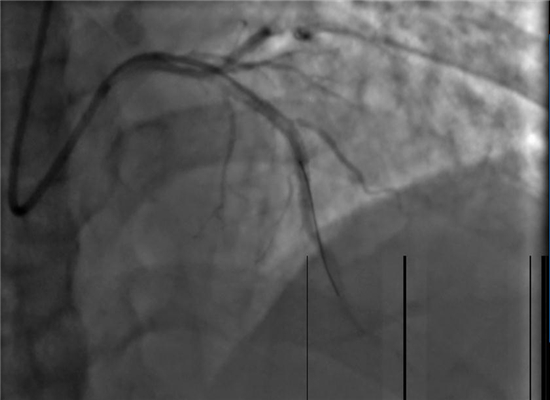

手术之后

在向患者家属详细说明手术的必要性及风险并征得同意后,杨勇主任带领科室介入手术团队迅速展开工作,将患者送入了导管室,并以最快的速度完善术前准备。23:02分开始手术,介入团队密切配合,快速穿刺桡动脉、置管、造影、开通闭塞血管,植入支架。经过约40分钟的全力救治,成功挽救了患者的生命。目前,术后患者症状明显改善,恢复较好。